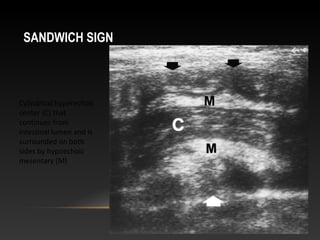

SANDWICH SIGN

Cylindrical hyperechoic

center (C) that

continues from

intestinal lumen and is

surrounded on both

sides by hypoechoic

mesentary (M)

-sandwich sign (longitudinal)